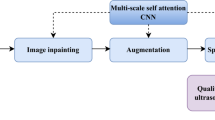

The existence of speckle noise in medical ultrasound (US) images greatly diminishes image quality and decreases diagnostic accuracy. The recent models for de-noising US images suffer from poor generalizability, a loss of texture information, and over-smoothing of the US images, especially at high noise levels. This study suggests an efficient and robust de-speckling filter for US images based on an attentional auto-encoder. This filter incorporates two distinct and efficient attention levels. The channel attention level (CAL) and large kernel attention level (KAL). These levels are integrated into the down-sampling and up-sampling steps, respectively. A skip link is added before the up-sampling stage to avoid the gradient vanishing during training. The performance of the introduced model was assessed using subjective visual evaluations and objective determination indices. The outcomes of the suggested approach on online databases achieved the minimum execution time (AET), the maximum values for structural similarity (SSIM), and peak signal-to-noise ratio (PSNR) indices over all levels of noise, exceeding other recent algorithms. For instance, at a high level of noise, the presented technique based on the breast database achieves the following mean values: 0.005, 0.81, and 23.71 dB for the AET, SSIM, and PSNR, respectively. Also, in clinical settings, the introduced model attained the highest values for the equivalent number of looks (ENL = 18.78), contrast-to-noise ratio (CNR = 5.12), and highest resolution (\(\alpha^{\sim }\) = 0.28). These findings prove that the presented architecture is more efficient and robust for rejecting noise while maintaining image details than other recent techniques.